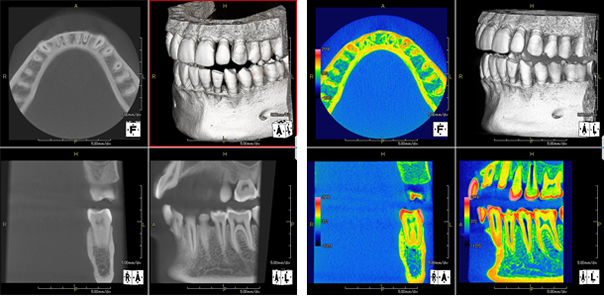

volumeをXYZ方向にそれぞれ512分割しておりこのときのスライスピッチは標準モード撮影で147㎛、高解像度モード撮影(ハイレゾ)で101㎛です。 3D画像はリアルタイムで自由に動かすことができるので骨の形態や奥行きを容易に把握できます。 さらにウィンドウレベルを操作することでさまざまな画像を簡単に得ることができます。 またインプラント治療においては下顎管やオトガイ孔、上顎洞下壁までの距離を正確に測定できるので術中も安全に治療をおこなうことができます。 |

| XYZ軸断層面(水平断、前頭断、矢状断と3DVR) |

| 高性能viewer |